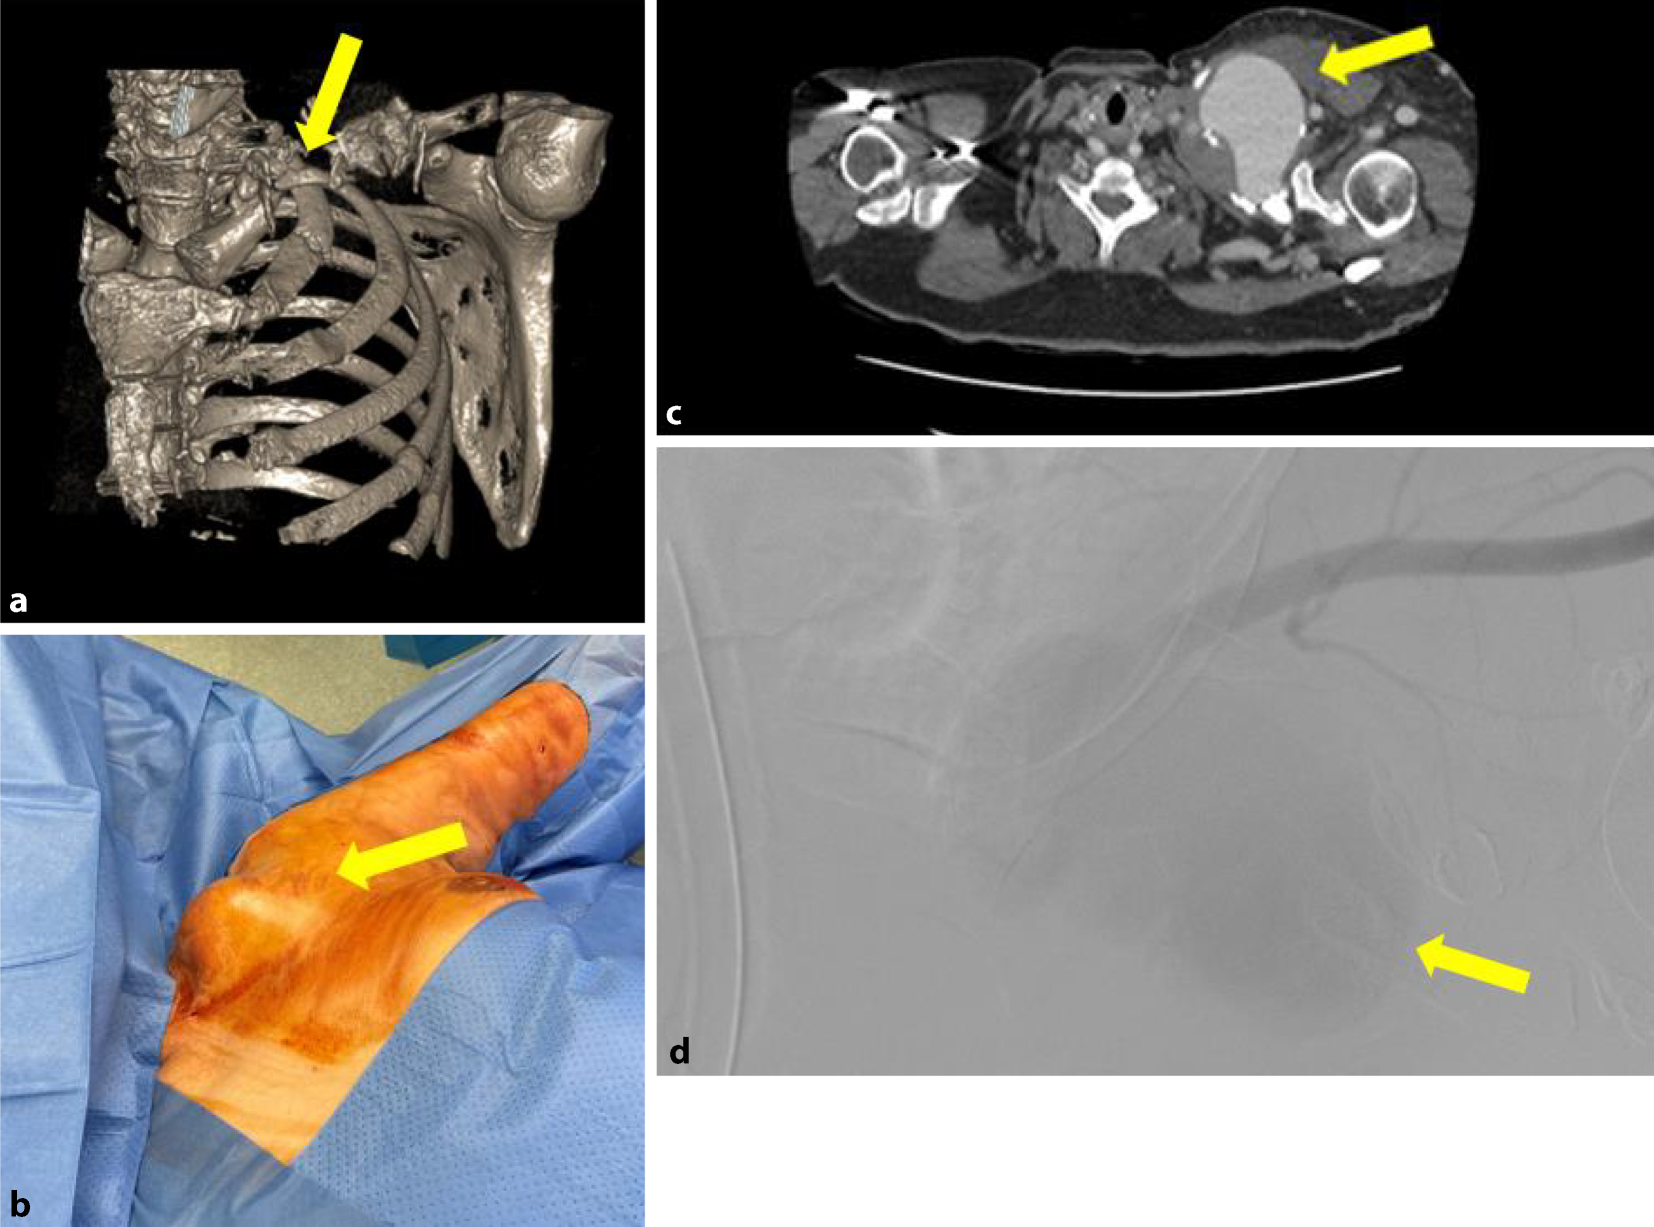

Die initiale Sonographie zeigte eine 7,1 × 7,2 cm echoleere Raumforderung mit echoreichen Thrombusformationen, in der farbcodierten Duplexsonographie mit einer pulssynchronen vollen Farbfüllung. Die konventionelle Nativröntgenuntersuchung der linken Schulterregion (und) die Knochenrekonstruktion einer Nativcomputertomographie (CT) dokumentierten eine ausgedehnte Osteolyse der Klavikula im mittleren Drittel, die eine Längsausdehnung von ca. 5–6 cm im Vergleich zur Gegenseite einnahm (Abb. 1a). Es ließ sich eine ausgedehnte Weichteilschwellung mit einem Durchmesser von 103 mm in dieser Region nachweisen (Abb. 1b). Die nachgeschaltete CT-Angiographie (CTA) zeigte im Bereich der linken Schulter ein ca. 8,6 × 7 cm großes Pseudoaneurysma, entspringend aus der A. subclavia sinistra, welches die Umgebungsstrukturen verdrängte (Abb. 1c).

Abb. 1

Fall 1: Pseudoaneurysma der A. subclavia links. a 3-D-Rekonstruktion des linksthorakalen CT-Scans, insbesondere der linken Klavikula mit Osteolyse im mittleren Drittel (gelber Pfeil), b präoperative Darstellung des linksklavikulären Lokalbefundes mit raumfordernder Wirkung (gelber Pfeil), c CT-Angiographie (transversale Schichtung) mit Nachweis des Pseudoaneurysmas links (gelber Pfeil), d digitale Subtraktionsangiographie der A. subclavia sinistra mit Nachweis des Pseudoaneurysmas (mattgrau – gelber Pfeil)

Eine komplettierende digitale Subtraktionsangiographie (DSA) identifizierte das Pseudoaneurysma, entspringend aus einem Defekt der A. subclavia sinistra (Abb. 1d).